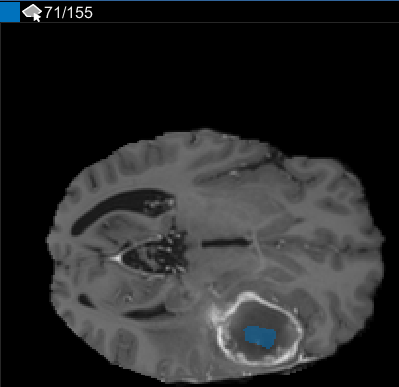

После использования интерполяции проверяйте отдельные срезы, чтобы видеть, создала ли интерполяция удовлетворительные ROI. Обратите внимание на то, что ROI на срезе 71 не заполняет целый объект, который вы хотите сегментировать. Можно вручную настроить ROI с помощью инструмента Paint Brush. В качестве альтернативы можно использовать один из инструментов на вкладке Automate. Например, можно использовать Активные Контуры, чтобы вырастить ROI на срезах, где это не заполняет полный размер опухоли.

В панели Среза перейдите к срезу, где объект сначала появляется, и начните помечать объект на каждом срезе с помощью инструмента для рисования. В следующем рисунке этот пример использует инструмент Paint Brush, чтобы пометить опухоль. Как ранее, можно чертить объект на каждом срезе, где это появляется, или используйте инструменты интерполяции, чтобы привлечь несколько срезов автоматически. После интерполяции можно использовать инструменты для рисования, такие как Средство стирания, чтобы изменить автоматизированную сегментацию на каждом срезе.